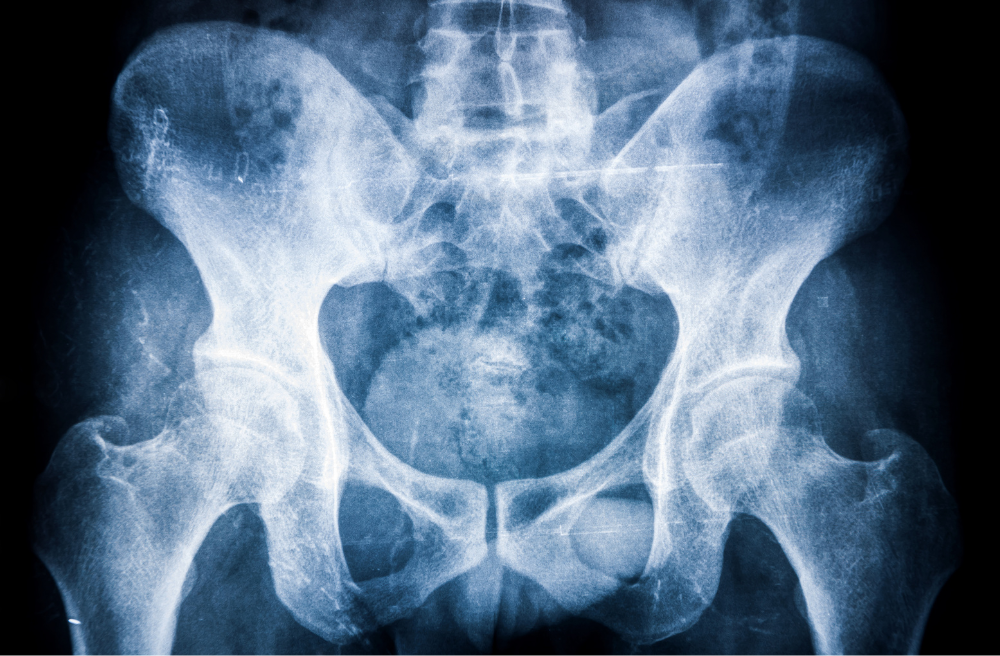

강직성 척추염은 주로 척추, 특히 꼬리뼈 부위의 천장 관절 쪽에 영향을 미치는 만성 관절염의 일종이지만 경우에 따라 다른 관절에도 영향을 미치곤 합니다.

강직성 척추염은 자가 면역성 염증 장애에 해당하는데, 쉽게 말하자면 우리 몸의 면역 체계가 반대로 우리 몸을 공격한다는 것을 의미합니다. 강직성 척추염에 의한 면역 체계 이상은 척추의 관절과 인대를 공격하여 염증과 손상을 일으키게 됩니다.